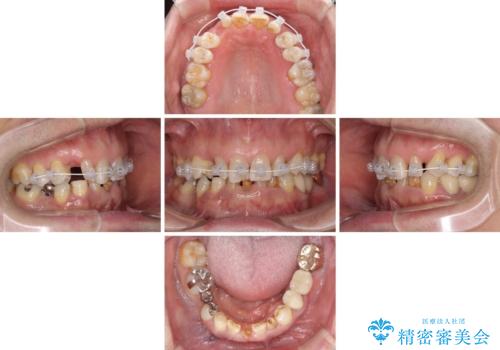

乳歯や矮小歯の多い前歯 部分矯正と補綴治療による審美歯科治療

- 乳歯や矮小歯が多くある前歯部の審美障害が気にして来院された患者様です。

上顎の矮小歯は隙間が多く、歯軸の傾斜も大きかったため、部分矯正により補綴治療前に歯の位置を整えることとしました。

下顎の乳歯は支台歯として機能することは困難と思われたので、事前に抜歯をし、上顎の矯正治療終了のタイミングに合わせて、セラミックブリッジにて補綴治療することとしました。

前歯部はディープバイトという、上顎前歯が下顎前歯に深く覆い被さる咬合であったので、理想的には全顎矯正が必要となりますが、今回は患者希望により前歯部のみの部分矯正で対応しました。そのため下顎犬歯の神経を取り除くことになってしまったのは心残りであります。